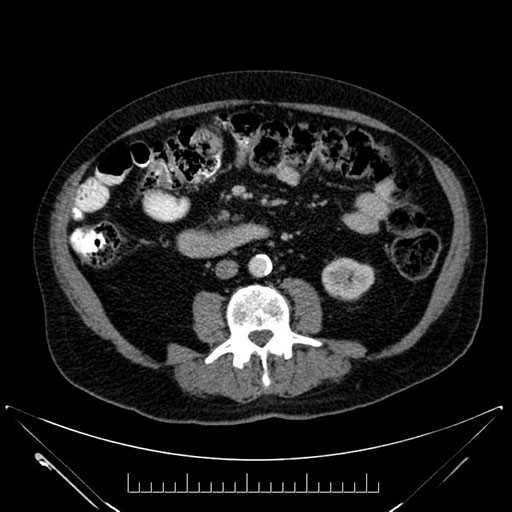

Look through the patient's CT scan to identify any areas of concern for the necessary procedure.

Imaging analysis

Based on your CT findings, which issue(s) would give reason for "planned slowing down moment(s)" in this case?

Considering a standard Whipple procedure, what step(s) of the operation would you do differently in this case?